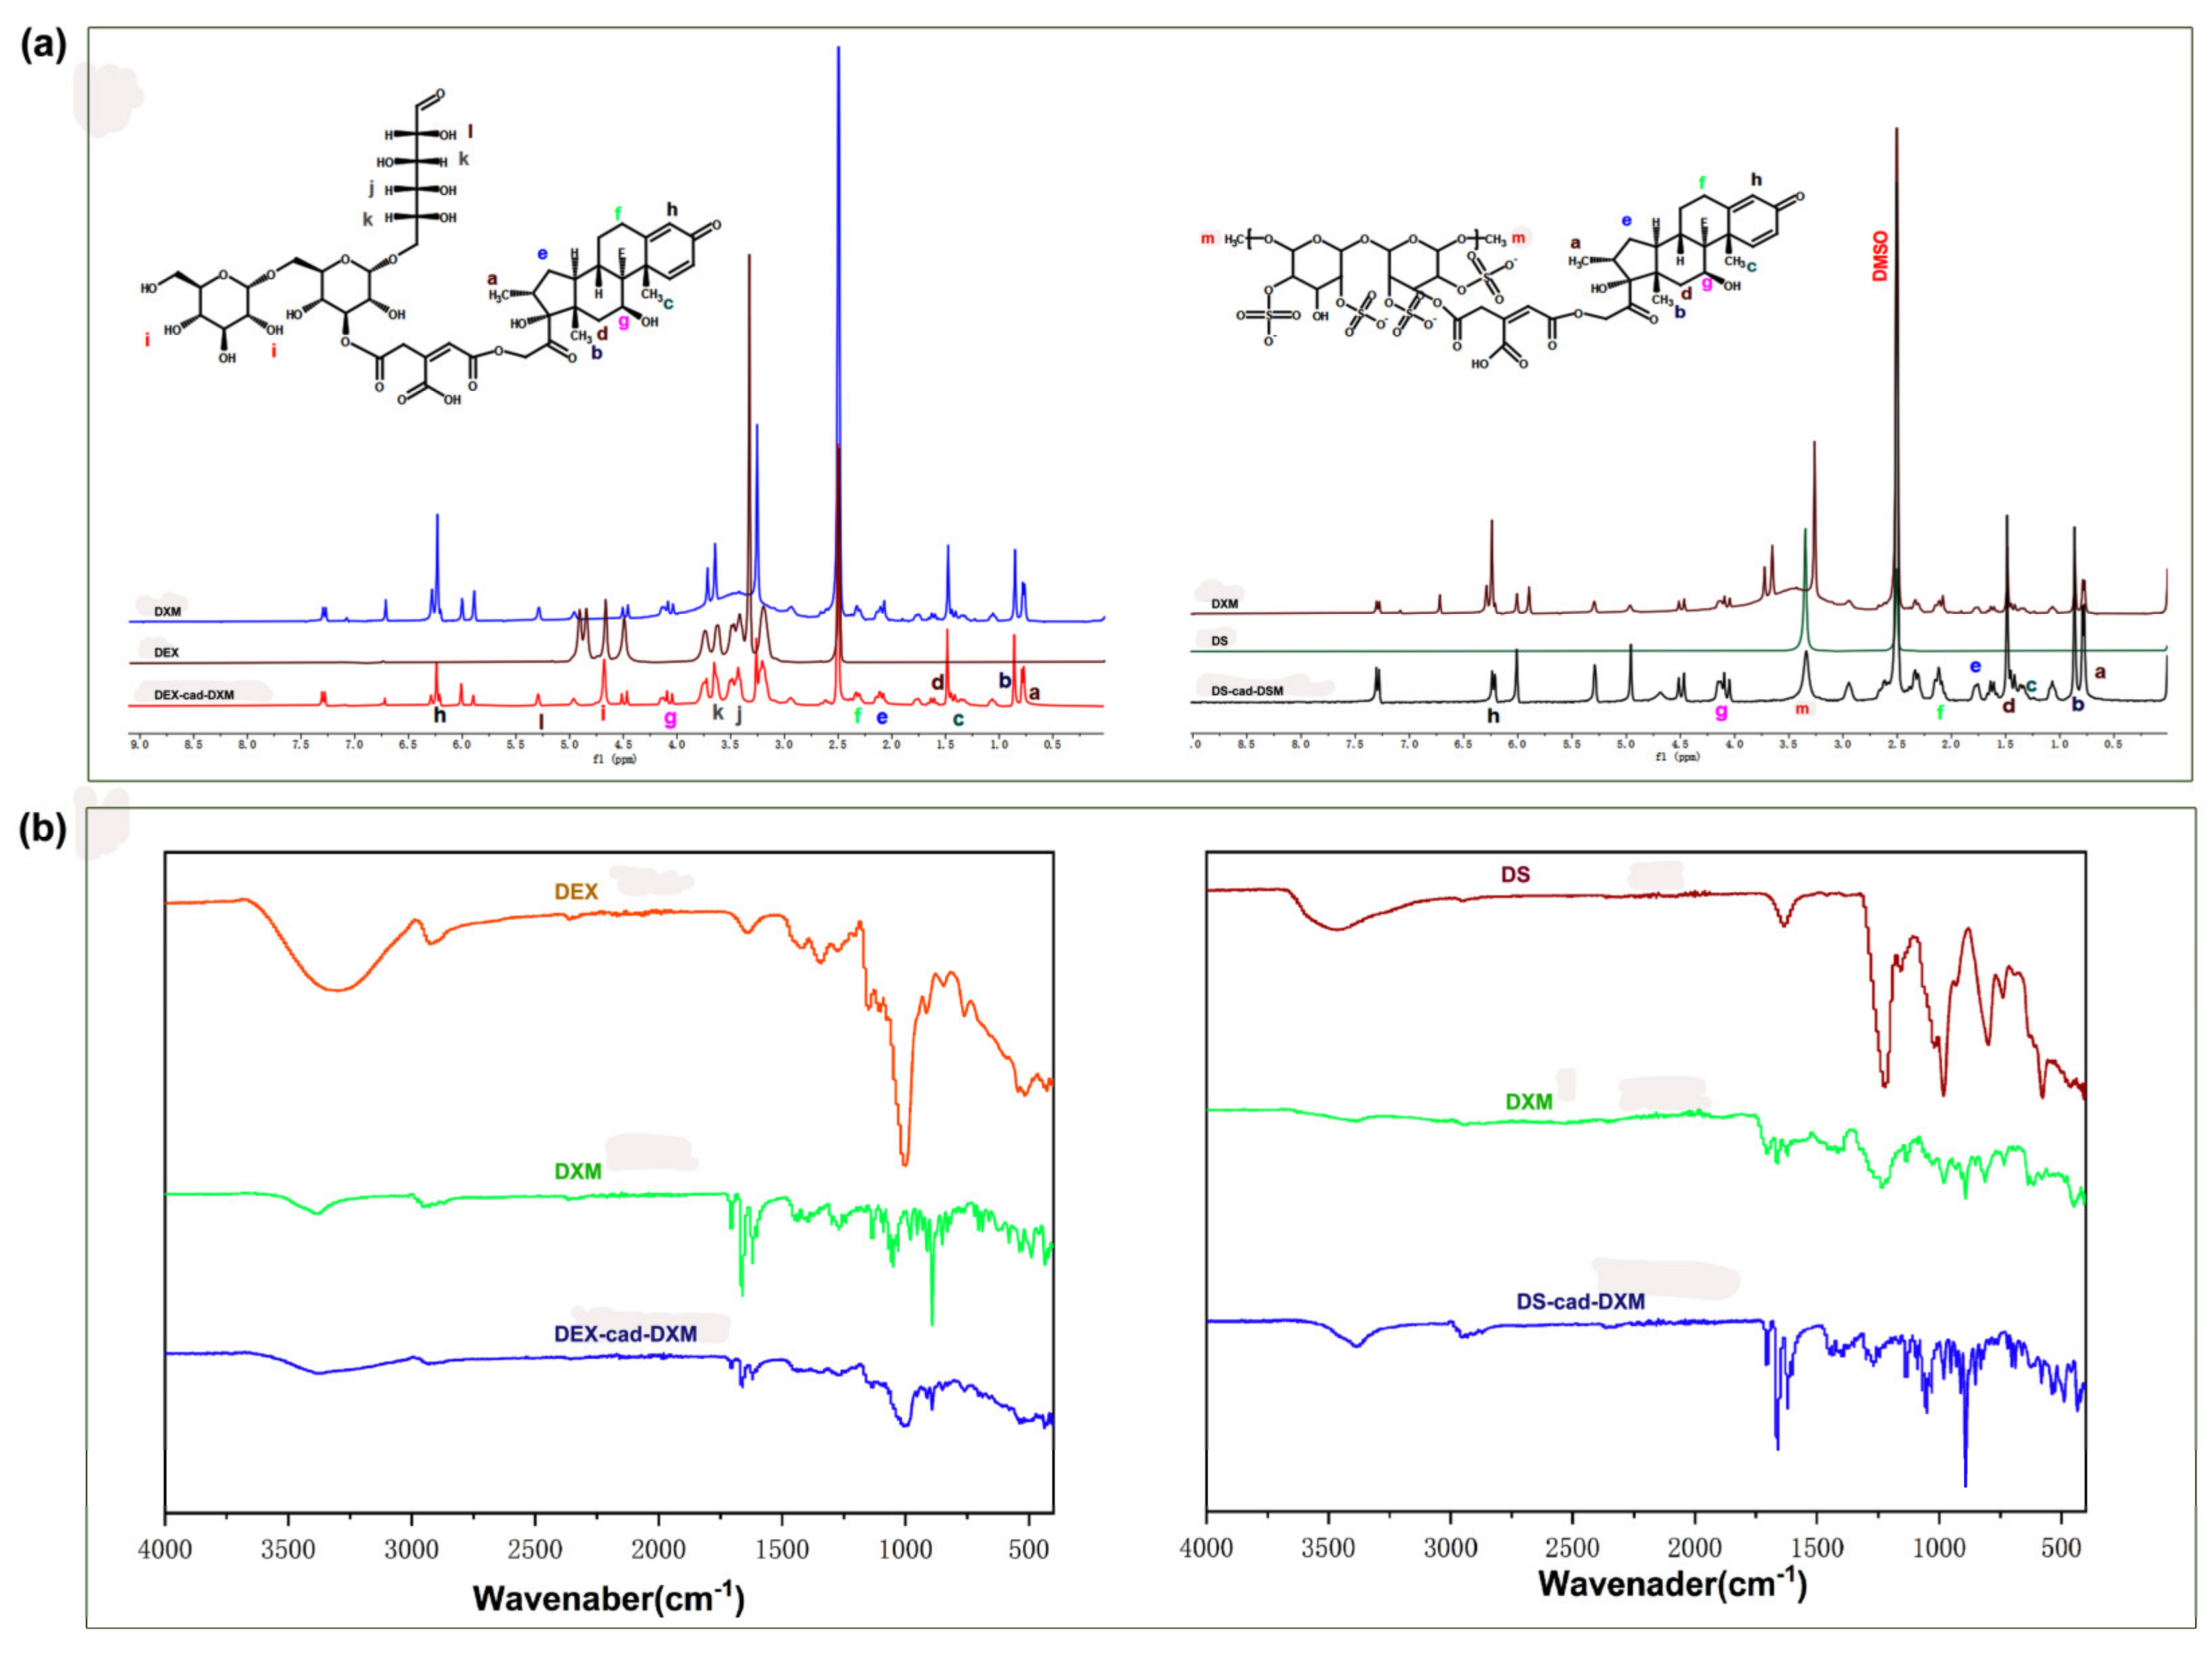

2.1. Characterizations of the Conjugates